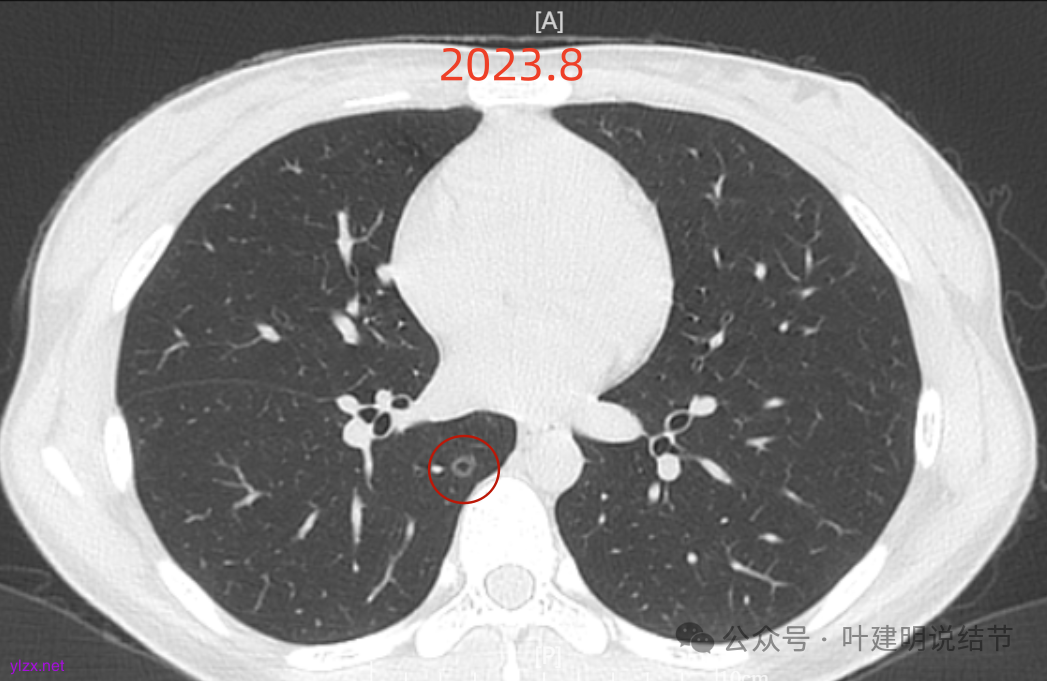

先来看2023年8月的:

病灶6:右下叶脊柱旁囊腔型病灶,整体轮廓与边界清,没有明显实性成分,考虑原位癌或微浸润性腺癌可能性大。